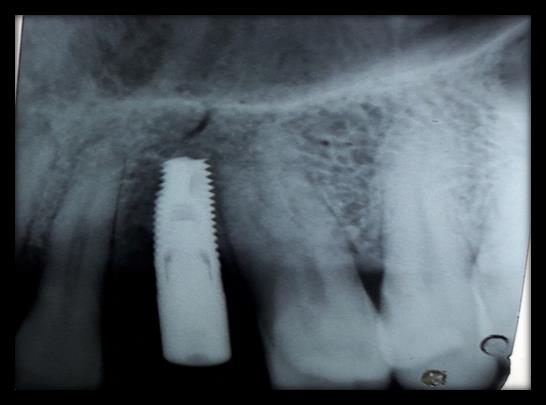

IMPLANT PLACEMENT